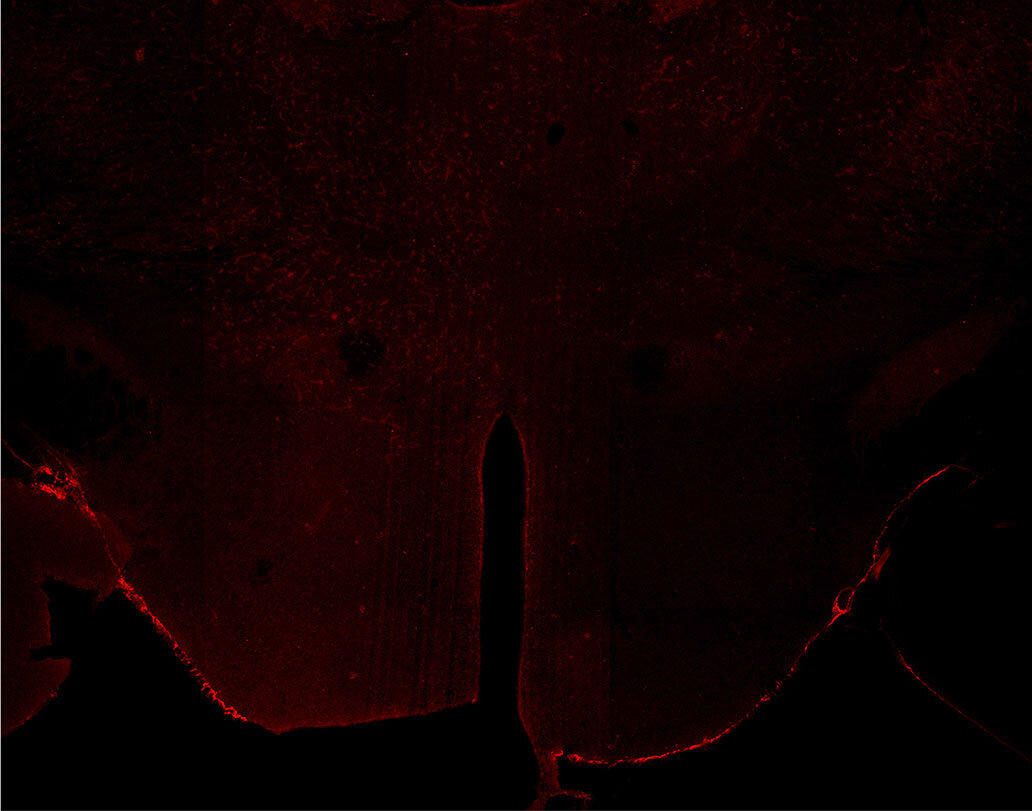

Indirect immunostaining of PFA fixed KO mouse brain sections

Indirect immunostaining of PFA fixed KO mouse brain section (hypothalamus) with Guinea pig anti-Orexin A (cat. no. 389 004, dilution 1:500 red).

Courtesy: Dana Mayer & Markus Fendt, Institute of Pharmacology and Toxicology, Magedeburg